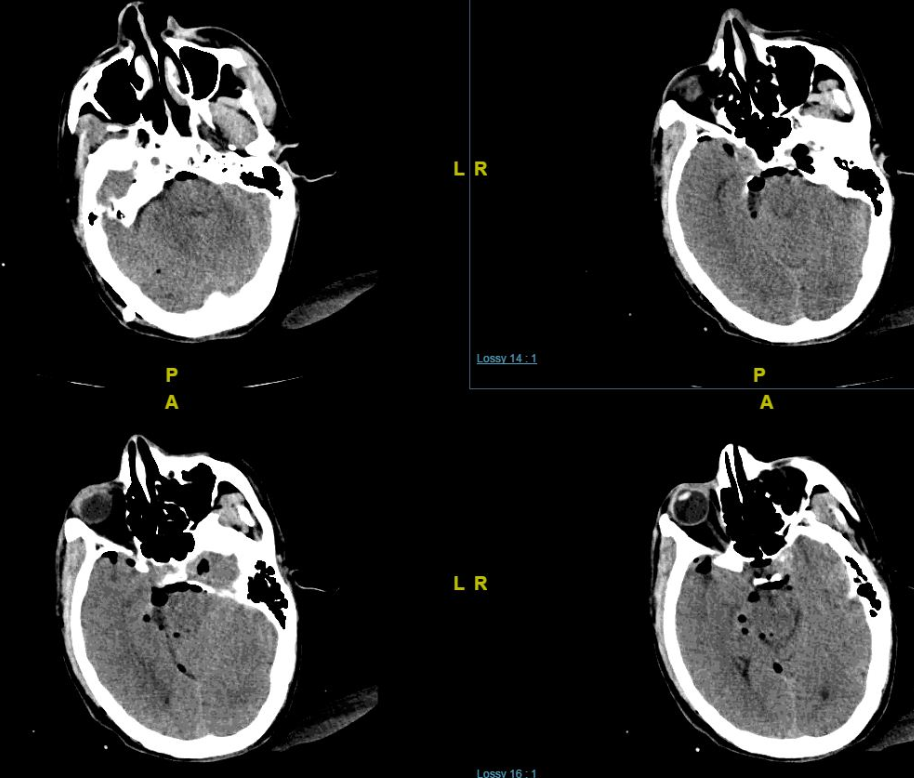

(a)轴位ct显示左侧岩尖不规则侵蚀和典型的虫蛀外观.